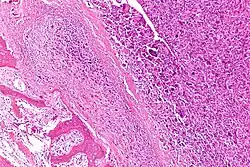

Intermediate-magnification micrograph of an osteosarcoma (center and right of image) adjacent to non-malignant bone (left-bottom of image): The top-right of the image has poorly differentiated tumor. Osteoid with a high density of malignant cells is seen between the non-malignant bone and poorly differentiated tumor (H&E stain).

Microscopically: The characteristic feature of osteosarcoma is presence of osteoid (bone formation) within the tumor. Tumor cells are very pleomorphic (anaplastic), some are giant, numerous atypical mitoses. These cells produce osteoid describing irregular trabeculae (amorphous, eosinophilic/pink) with or without central calcification (hematoxylinophilic/blue, granular)—tumor bone. Tumor cells are included in the osteoid matrix. Depending on the features of the tumor cells present (whether they resemble bone cells, cartilage cells, or fibroblast cells), the tumor can be subclassified. Osteosarcomas may exhibit multinucleated osteoclast-like giant cells.[22]